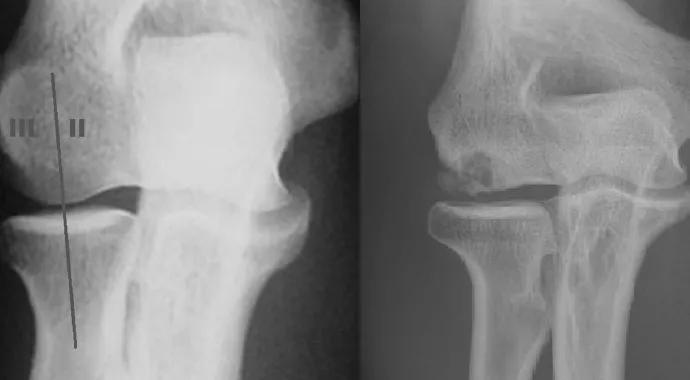

Figure 1. (left) A 45-degree flexed, supinated anteroposterior X-ray view of an elbow with type II (medial) and type III (lateral) OCD lesions. Reprinted from Kolmodin and Saluan.2. Figure 2 (right). X-ray of an elbow with a type IIIb OCD lesion. Reprinted from Kolmodin and Saluan.

Type IIIb lesions (“unstable”) are those with a closed capitellar physis, a grade II/III radiographic profile or presentation with restricted elbow ROM, and a location lateral to the radial head centerline, including the lateral cartilage margin. These lesions require reconstruction, which enhances stability and reduces shear forces experienced by the lateral capitellum.